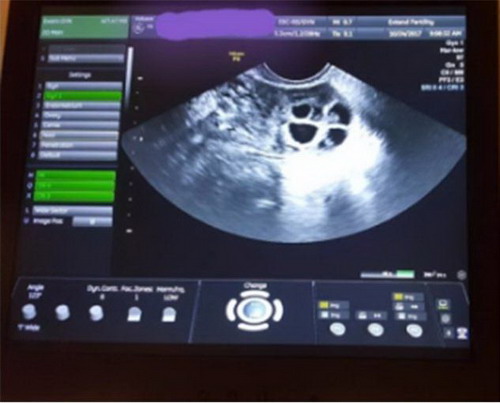

在格莱宝美孕科学医生的专业指导下,我进行了前期验血、阴超以及常规体检,结果令人给外惊喜

就这样,我正式开启了自己的冻卵之旅。我从来没有如此频繁的去医院,早上检查FSH、E2和卵泡发育等指标,晚上按照医生要求打针,这也是我第一次拿起注射器

经过十多天的促排,我的卵泡长到18mm。我躺在了取卵的手术台上,在麻醉药的作用下,我见见失去了意识。迷迷糊糊中,我梦到躺在一片漂亮的花海里,身边还有一个非常可爱的baby